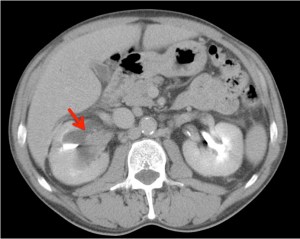

Paciente de 59 años con antecedentes personales de Cá de vejiga.

Se le realiza una Uro-Tc por seguimiento al año, aunque en esta ocasión el paciente refiere episodio de hematuria.

Tras el tratamiento de la recidiva y nefrostomía para la hidroureteronefrosis, vuelve acudir al hospital a los 9 meses por episodio de dolor en FD y malestar general. Se realiza una ecografía de urgencias.

Se realiza nueva TC bifásico abdominopélvio y Uro TC.

- Paciente con numerosas recidivas por Cá vejiga.

- Ha desarrollado un tumor metacrónico en pelvis renal derecha, también responsable de la hidroureteronefrosis.

- Mala evolución radiológica del proceso a expensas de metástasis pulmonares y hepáticas.